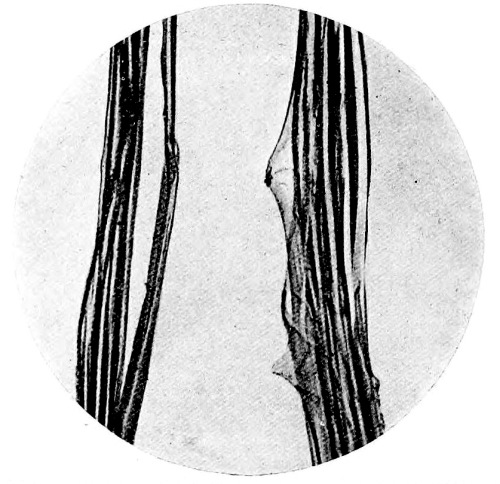

Plate showing Centre of Ossification in the Lower Epiphysi of PAGE

Femur in full time Fœtus To face 64

A plate, showing the centre of ossification in the lower epiphysis of the femur in a full time fœtus, has been introduced at the last moment, and will be found opposite page 64. References to the subject may also be found on pages 33 and 174.